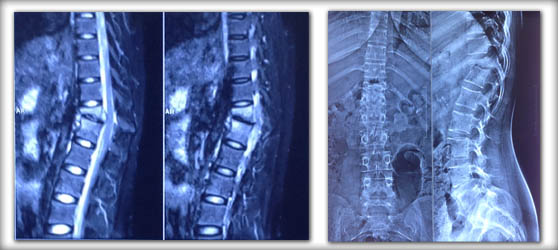

Infection occuring in the disc space is called as spondylodiscitis. Most commonly the infection is due to tuberculosis and rerely by other bacterias and fungus.

Patient will have pain , fever , loss of weight and loss of appetite. In severe case weakness can also develope.

Investigations needed are basic blood investigations( complete hemogram,CRP) X-ray and MRI. Biopsy ( testing the infected tissue) is needed to find out the organism causing the infection.

For initial stages of infection antibiotic medicines along with supportive appliances such as belt/ collar and orthosis is needed. In later cases with severe pain , deformity and weakness surgical intervention is needed. In case of tuberculosis infection 9 months of drug intake is needed.